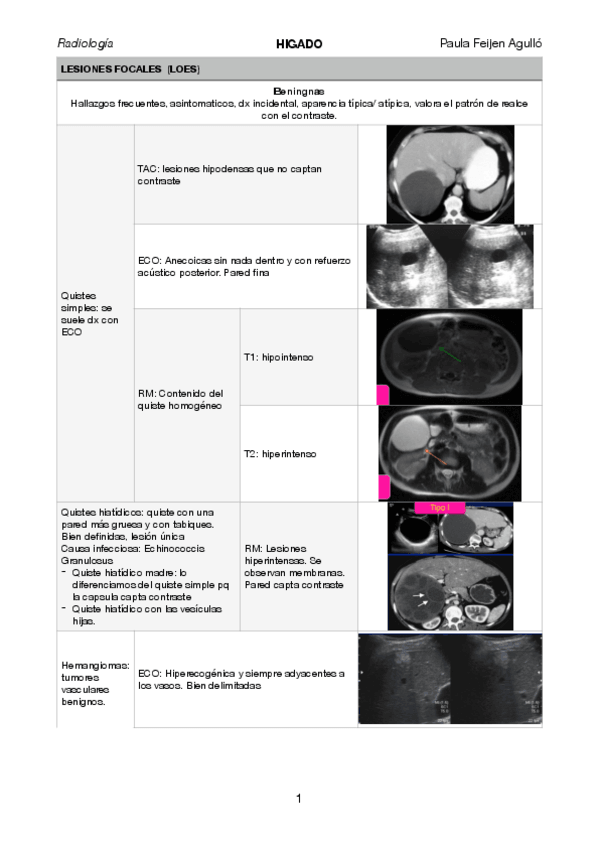

12 páginas

higado.pdf